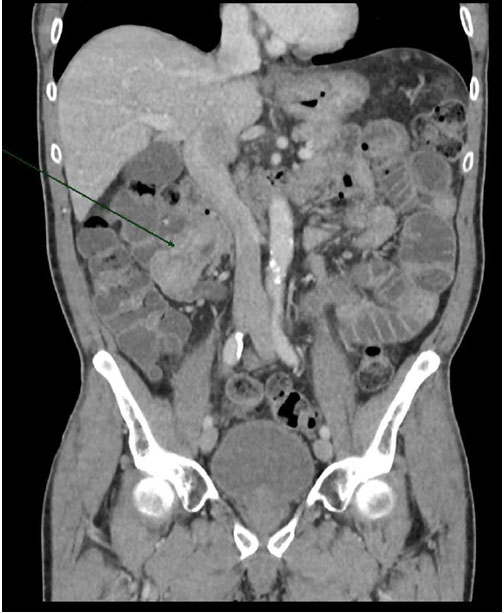

His abdominal examination revealed localized sign of peritonism. Apart from raised serum lactate 2.45 mmol/L and deranged LFT with ALT 174 U/L and AST 221 U/L, the rest of the blood results were within normal limit. Computed tomography scan of abdomen and pelvis demonstrated an enteroenteric intussusception in the right mid abdomen resulting in partial bowel obstruction with mild dilated loops of proximal small bowel (Refer Figure 1 and Figure 2). There were no evidence of perforation. No mass lesion was clearly identified within the bowel; however, an incidentaloma in the right adrenal gland was found, measuring 48 × 62 mm. The liver, gallbladder, pancreas, spleen, and both kidneys were unremarkable. There was no periaortic or mesenteric lymphadenopathy noted.

Figure 2: Sagittal view of CT abdomen pelvis of the enteroenteric intussusception.